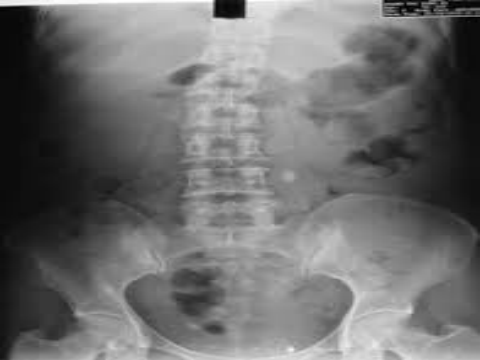

Kết quả phẫu thuật nội soi hông lưng lấy sỏi niệu quản đoạn lưng tại 62 Bệnh viện Đà Nẵng